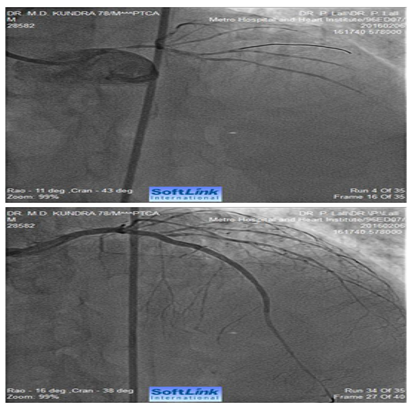

Figure 4 Caudally angulated RAO view of an 80 years old male showing extensive calcification involving distal LMCA extending into ostial LAD and ostial and proximal LCX (bifurcation lesion). The right panel shows fully opened-up LMCA, LAD and LCX after RA with a 1.25 mm burr and deployment of two drug eluting stents (one from LMCA to LAD and second one in proximal LCX (covering its ostium).